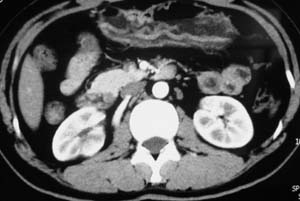

以下是引用子期在2010-3-19 20:47:00的发言:[br]血管畸形的ct增强应该有明显强化,本例并不相符合。本例双肾局部的略低密度影,累及肾盂,局部皮质明显变薄、内陷,增强扫描有轻度的强化,应考虑为炎性病变,患者为年轻男性,累及双肾的感染以结核较常见,可以没有明显的临床症状,尿中有时候也并不能查出什么;肾脓肿常有明显感染中毒症状,本例不符,另外一般的肾盂肾炎或肾小球肾炎通过小便就可确诊,其它还不能排除的是黄色肉芽肿性肾盂肾炎,然而单凭ct一般也很难鉴别。